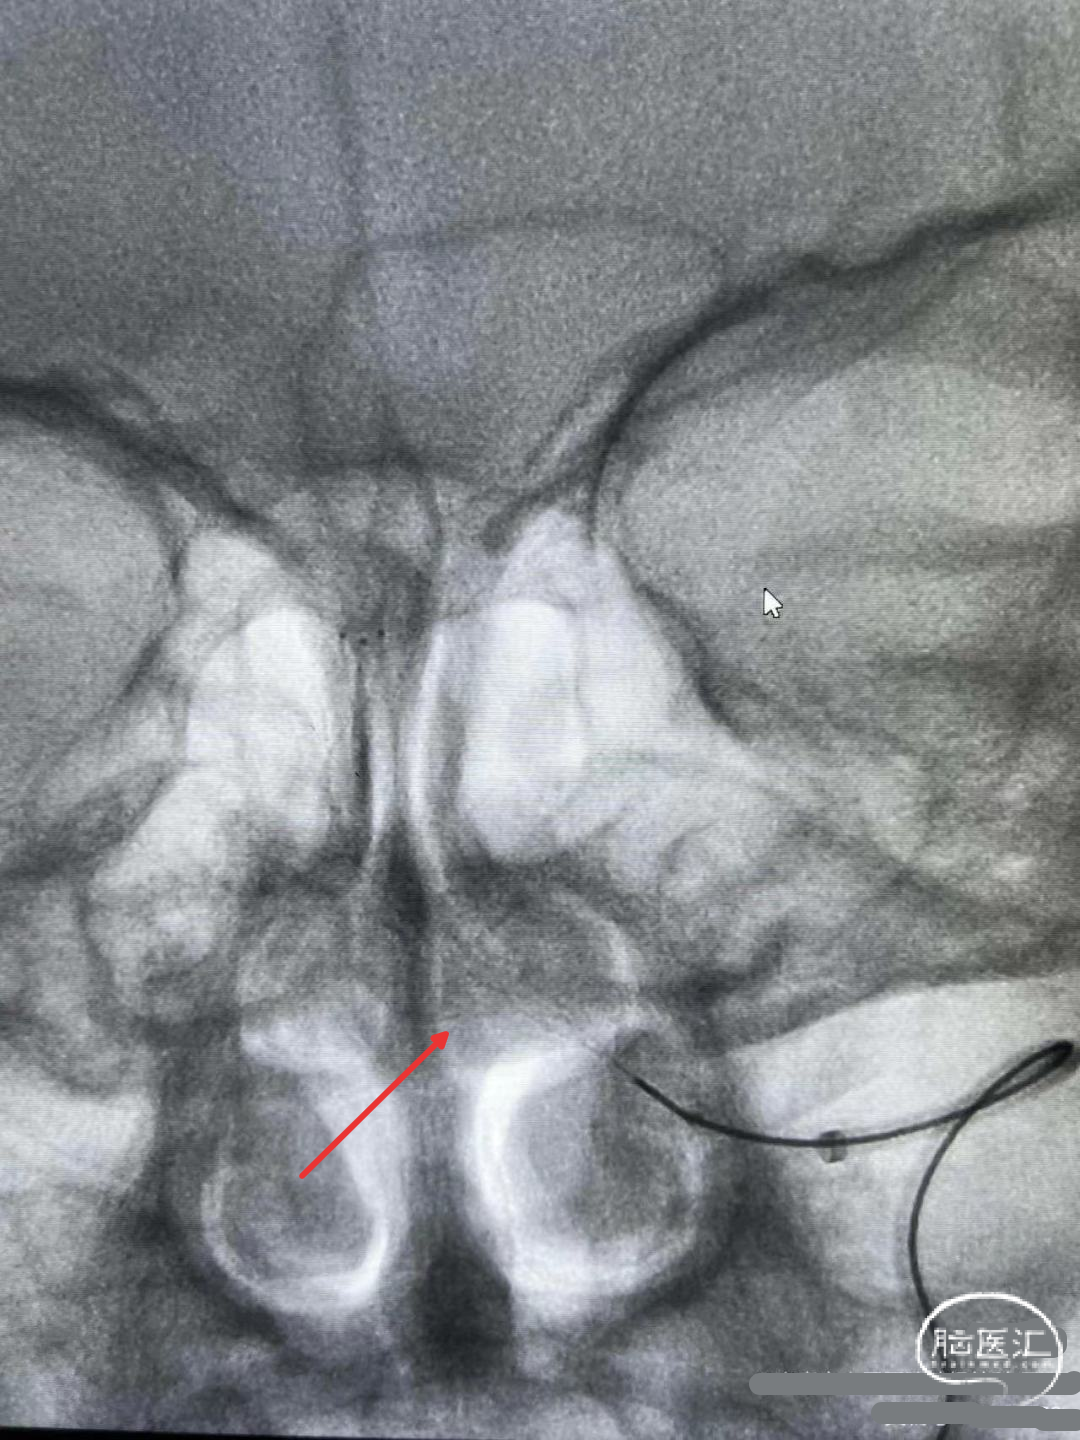

微导管到位及微导管造影:

微导管造影,确认在真腔。

操作要点:

判断闭塞位置及长度,选择合适规格支架。